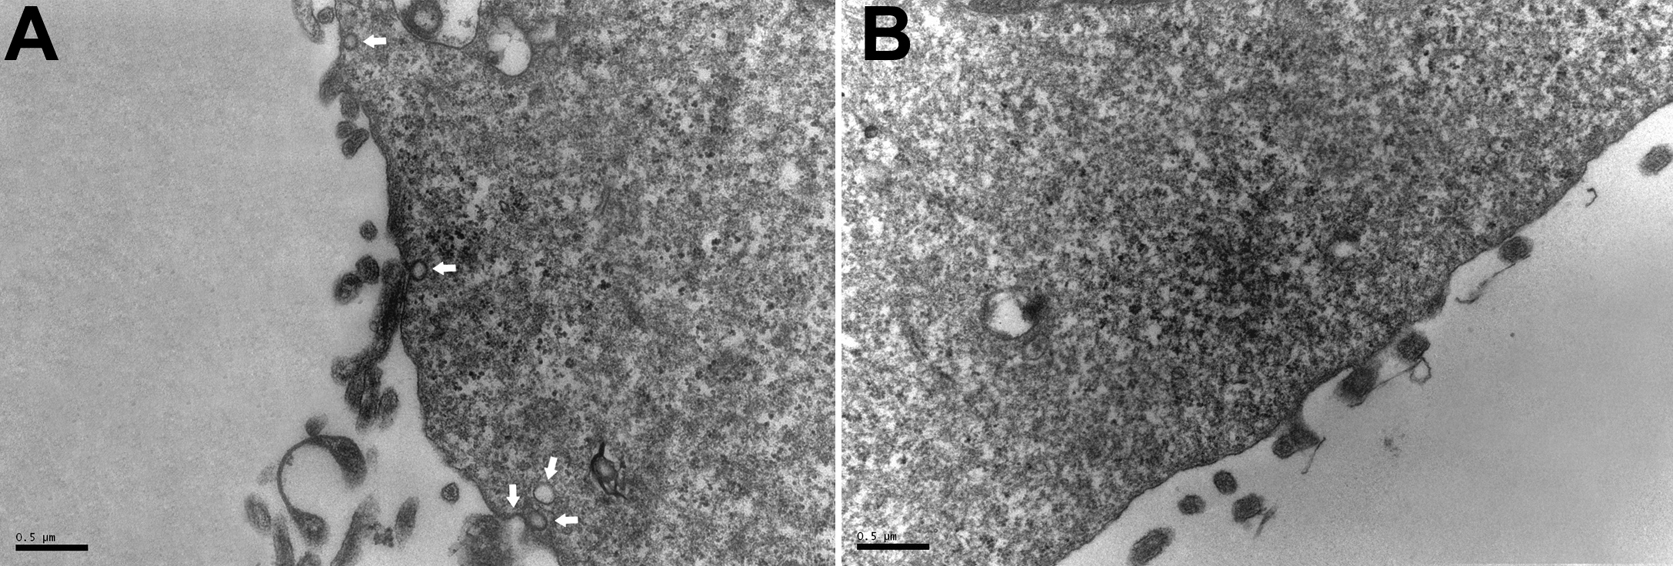

Figure 5. Transmission electron microscopy

of caveolae in HLE-B3 cells treated with high concentrations of

glucose. Cells were seeded on glass coverslips, treated with 5 mM or 25

mM glucose for 48 h, fixed with glutaraldehyde, post-fixed with osmium

tetroxide, and stained with uranyl acetate and lead citrate. A:

5 mM glucose-treated (control) cells. Arrows point to caveolae. B:

25 mM glucose-treated cells.